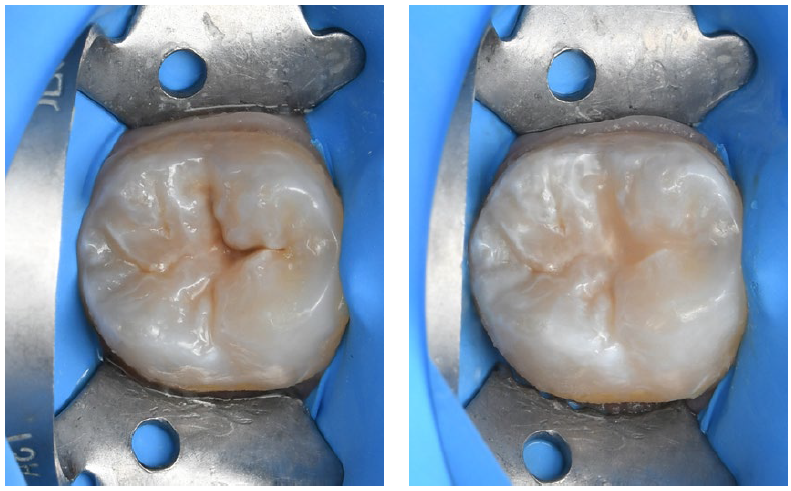

Fig. 2: Restoration of two molars: Teeth preparation and caries excavation.

Fig. 3: Restoration of two molars: Filling of the proximal and occlusal cavities.